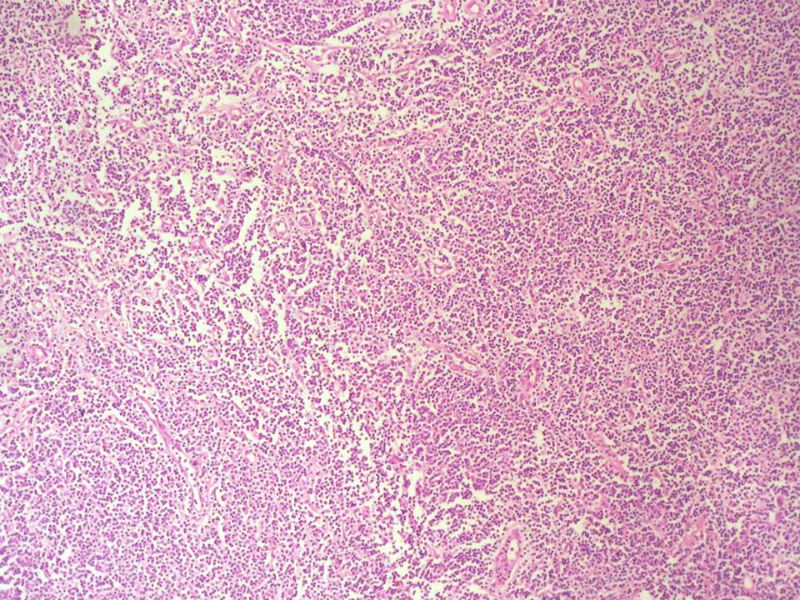

淋巴样细胞。细胞形态单一,细胞小。主要鉴别:

1)粘膜相关淋巴组织淋巴瘤

2)小细胞性淋巴瘤/慢性淋巴细胞性白血病

3)套细胞淋巴瘤

形态结构与细胞大小,似不支持滤泡性淋巴瘤。

上级医院会诊意见:

CD20(+),Kappa(+),ki-67(+)>2%,Lambda(+),Pax-5(+),符合粘膜相关淋巴瘤。

本例是发生在特殊部位“结膜下”,HE肿瘤细胞形态形态一致,形似单核样B细胞。B细胞标记若明确阳性,诊断MALT是挺合理的。